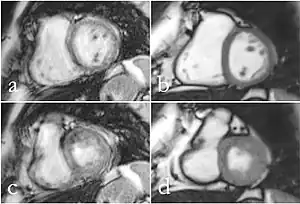

Standard reconstruction (left) versus reconstruction with DL (right) for a T2-weighted turbo spin-echo scan of the prostate

Machine learning

Image reconstruction in RT-MRI benefits from machine learning (ML) or deep learning (DL). A nonlinear kernel, or mapping function, can be developed from the ACS to fill in k-space data and generate the final image.[35] This process as a whole significantly accelerates the MRI process. Image segmentation or identification of lesions can be achieved through machine learning. In deep learning, with a convolutional neural network, the mapping function can be specified by the network. ML and DL improve image resolution as well as imaging speed.[35]